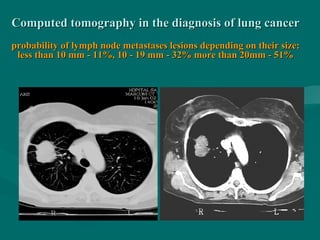

Computed tomography in the diagnosis of lung cancerComputed tomography in the diagnosis of lung cancer

probability of lymph node metastases lesions depending on their size:probability of lymph node metastases lesions depending on their size:

less than 10 mm - 11%, 10 - 19 mm - 32% more than 20mm - 51%less than 10 mm - 11%, 10 - 19 mm - 32% more than 20mm - 51%

Computed tomography inthe diagnosis of lung cancerComputed tomography in the diagnosis of lung cancer probability of lymph node metastases lesions depending on their size:probability of lymph node metastases lesions depending on their size: less than 10 mm - 11%, 10 - 19 mm - 32% more than 20mm - 51%less than 10 mm - 11%, 10 - 19 mm - 32% more than 20mm - 51%